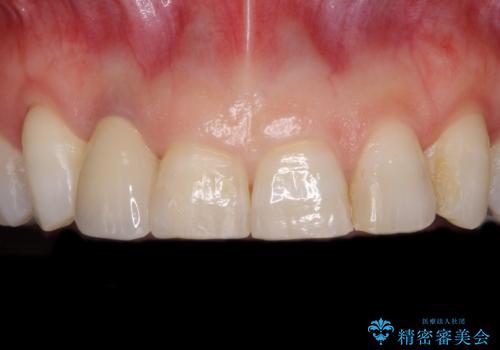

- 矯正治療中に装着していた仮歯を綺麗にしたいとのことで来院された患者様です。

小学生の頃に歯をぶつけて抜歯となりブリッジを装着したそうですが、その後矯正治療を行うに当たりブリッジを切断したとのことでした。

歯肉ラインを整えるために歯肉移植術を行うか悩んでいましたが、行わないという判断をされたため、やや不揃いの歯肉ラインとなりました。